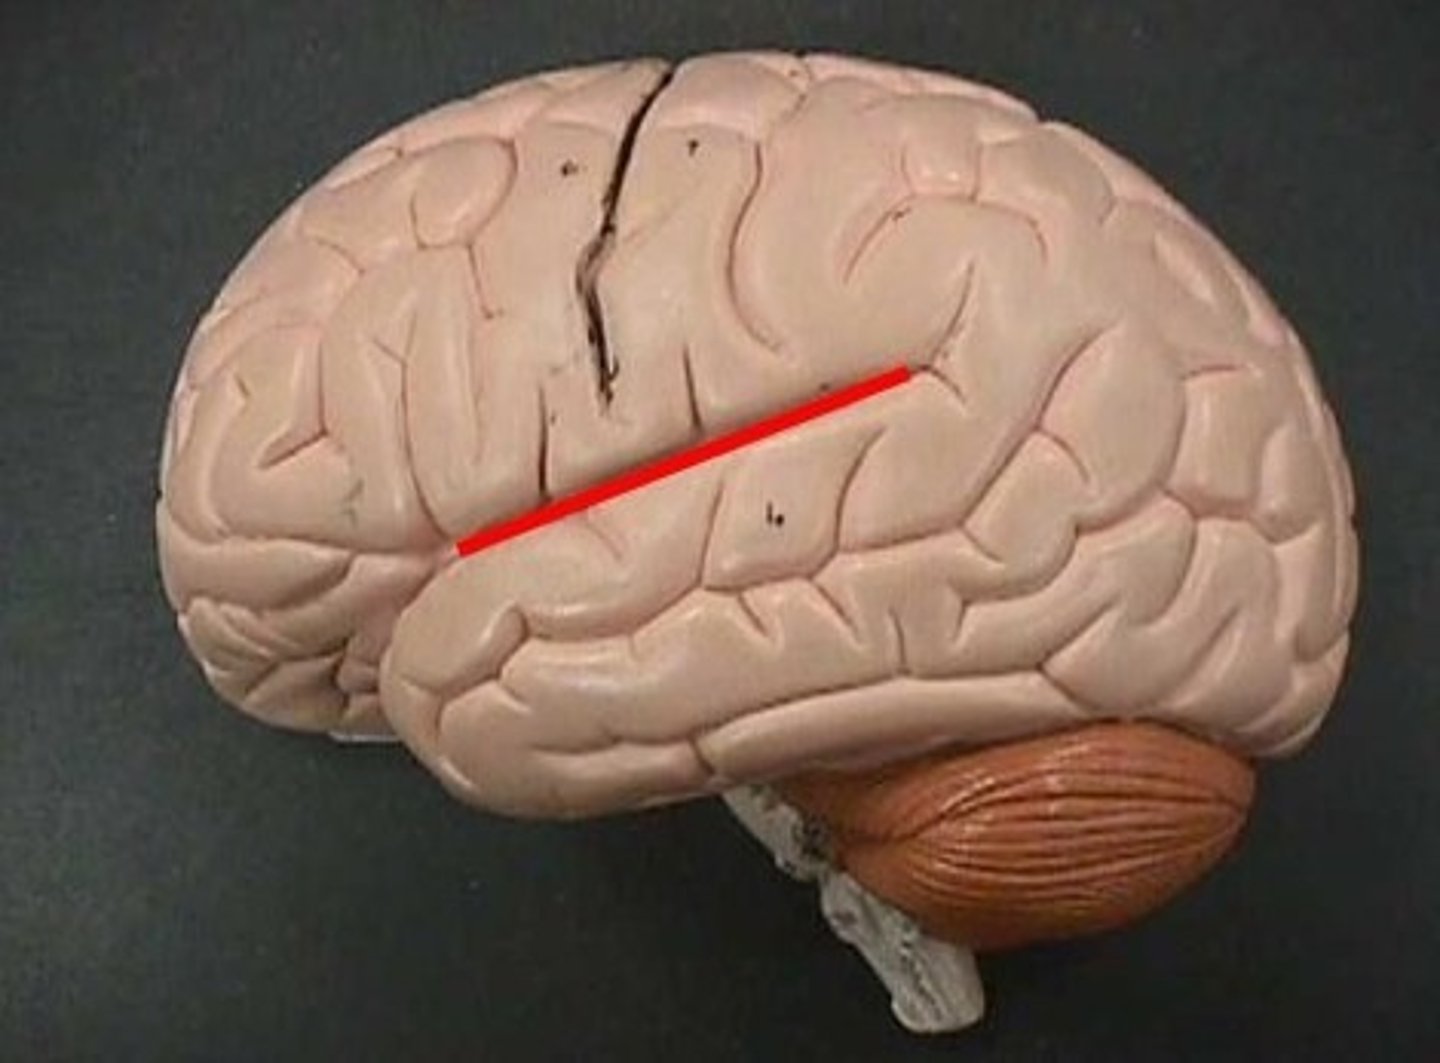

central sulcus

separates frontal and parietal lobes

lateral sulcus

Separates temporal lobe from parietal and frontal lobes

postcentral gyrus

the strip of parietal cortex, just behind the central sulcus, that receives somatosensory information from the entire body

superior temporal gyrus

the large gyrus of the temporal lobe adjacent to the lateral fissure; the location of auditory cortex